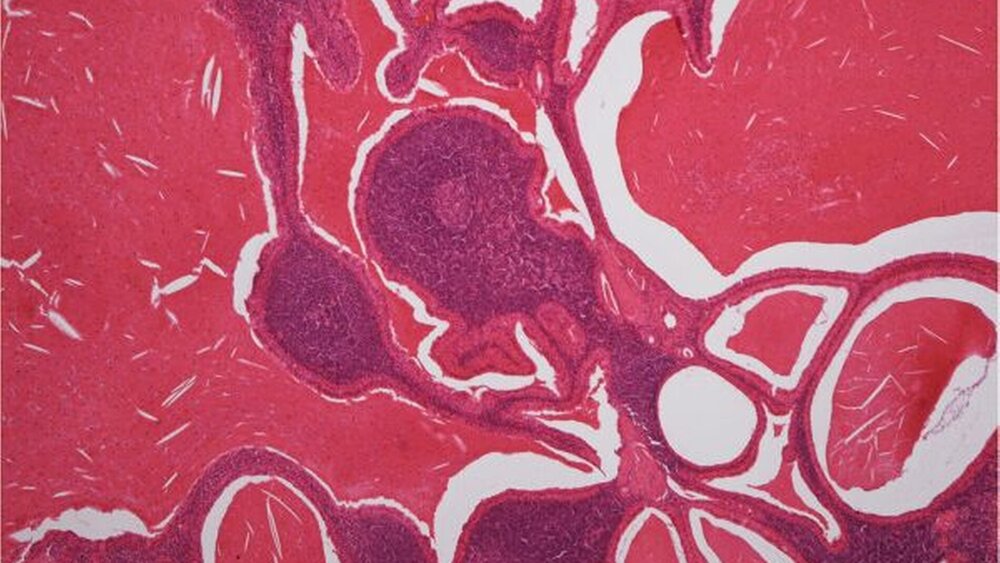

In Intubationsnarkose wurde die Raumforderung im Sinne einer lateralen Parotidektomie entfernt (Abbildung 3). Bei Anschnitt der Befunde entleerte sich teils klares, teils trübes Sekret, wobei die Schnittflächen neben zystischen, teils gelblich-bräunlich solide Anteile aufwiesen (Abbildung 4). Die histopathologische Aufbereitung des Präparats bestätigte die Verdachtsdiagnose eines Warthin-Tumors (Abbildung 5).

Die meist gut umschriebenen ovalen Warthin-Tumore, aus denen häufig eine klare bis bräunliche Flüssigkeit austritt, zeichnen sich histopathologisch durch eine dünne Kapsel und im Inneren durch Faltelungen mit zystischen Hohlräume aus, die von einer zweilagigen Schicht onkozytärer Epithelien ausgekleidet sind. Das Stroma enthält reichlich polyklonal, lymphatisches Gewebe mit Keimzentrumsbildung.